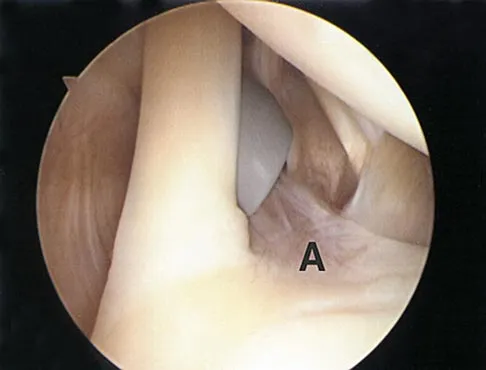

A football player sustains a traumatic anterior inferior dislocation of the shoulder in the last game of the season. It is reduced 20 minutes later in the locker room. The patient is neurologically intact and has regained motion. If the patient undergoes arthroscopic evaluation, what finding is seen most consistently?

Explanation